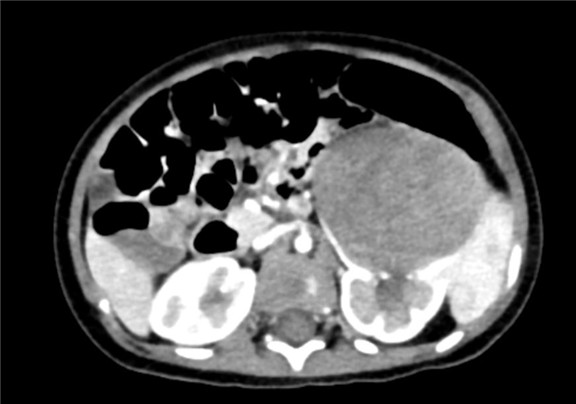

上腹部增强CT:左肾巨大占位性病变,疑似肾母细胞瘤

术前CT检查:

动脉期

静脉期

平衡期